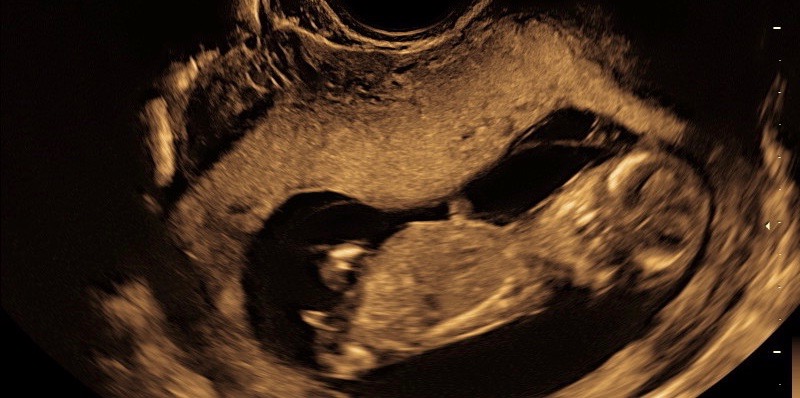

*****EDITED TO ADD SECOND PIC, as bigpinkwish kindly pointed out first MIGHT be UC:)***

Attachment 37754

I've attached a second pic, just in case what I thought was nub was actually umbilical cord, as bigpinkwishpointed out:)

Does this change anything or still boy?

Thanks so much ladies!